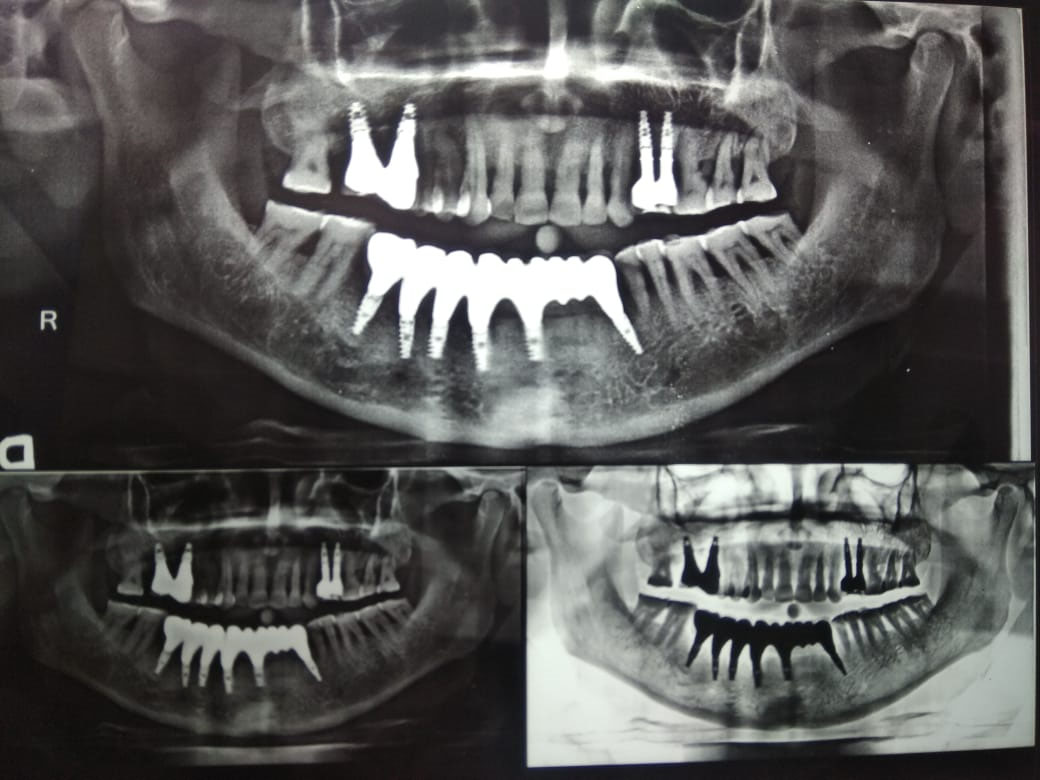

Attachment loss around teeth in the partially edentulous patient increased further to around 3.5-4 mm. There was no implant loss, prosthesis complications like ceramic fracture and unscrewing of abutments in both patients (Figures 9 and 10).This could be attributed to follow-ups at regular intervals.

japid-11-39-g009

Figure 9. 10-year follow-up for the completely edentulous patient.

japid-11-39-g010

Figure 10. Follow-up for the partially edentulous patient.